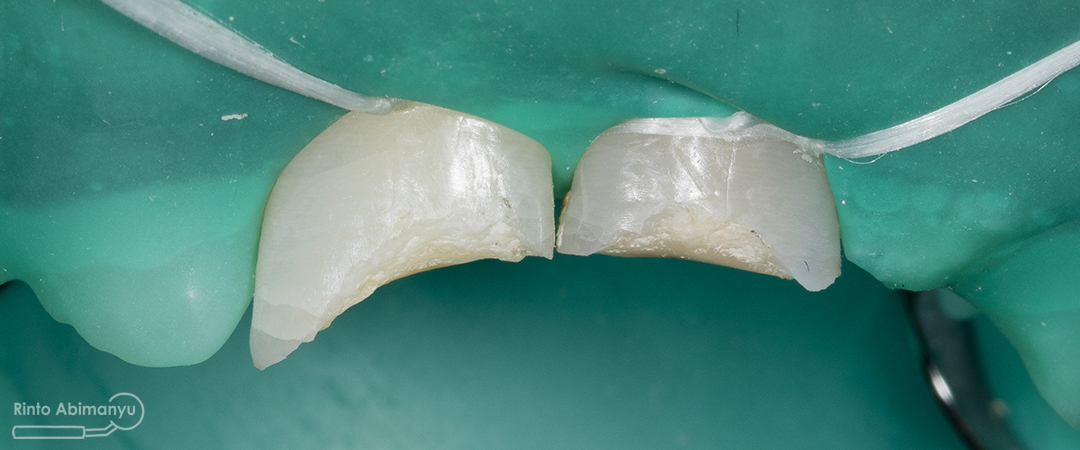

Begini kondisi klinis saat datang…

Foto klinis gigi-gigi anterior yang mengalami fraktur